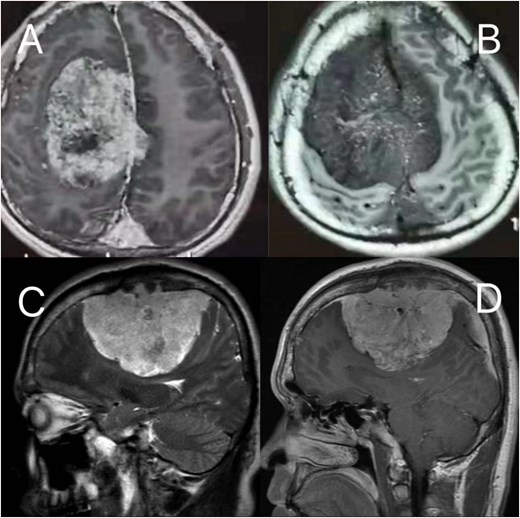

A 23-year-old male presented to our hospital with a 3-day history of episodic left upper limb paralysis. Upon admission, he reported progressive left lower limb motor incoordination, temporal visual field defects in the left eye, bilateral vision,deterioration, and bilateral olfactory hypesthesia over the preceding 3 months. Three days prior to admission, he experienced sudden-onset left upper limb paralysis lasting ~10 minutes before spontaneous resolution. Cranial magnetic resonance imaging (MRI) revealed a giant meningioma (>8 cm in diameter) causing extensive compression of adjacent structures, with marked heterogeneous enhancement on contrast imaging (Fig. 1). Preoperative intracranial vascular embolization was performed, followed by tumor resection via a bifrontal-parietal approach 1 day later (Fig. 2). Intraoperative findings confirmed a tumor >8 cm in diameter with cranial bone erosion (Fig. 3). Postoperatively, the patient developed transient bilateral lower limb paralysis (muscle strength grade 0) on Day 1, which resolved completely within one month. Histopathological analysis demonstrated features consistent with atypical meningioma: sheet-like growth pattern, increased nuclear-to-cytoplasmic ratio, prominent nucleoli, focal necrosis, and immunohistochemical staining showing Vimentin(+), SSTR2(+), PR(+), EMA(−), and a Ki-67 proliferation index of 5%–10%. The patient underwent gamma knife radiosurgery at 6 months and 1 year postoperatively. Three-year follow-up MRI showed no tumor recurrence or significant progression of residual lesions (Fig. 4), with significant improvement in visual acuity, hearing, and visual field deficits.

Preoperative MRI: (A, B) axial post-contrast T2-weighted and T1-weighted, respectively (C, D) sagittal position post-contrast T2-weighted and T1-weighted, respectively. The MRI findings describe a lesion in the right frontoparietal region adjacent to the superior sagittal sinus, measuring ~8.6 × 8.2 × 6.9 cm. The lesion demonstrates long T1 and T2 signal characteristics and exhibits marked heterogeneous enhancement on contrast-enhanced scans. It encircles the superior sagittal sinus and extends across the cerebral falx to the contralateral side, with multiple tortuous flow-void vascular shadows observed within and around the lesion. The mass is broadly attached to the adjacent calvarium, invading the diploic layer of the skull. Posteriorly, it extends along the superior sagittal sinus to the origin of the left transverse sinus. Compression of adjacent brain parenchyma results in irregular narrowing of the lateral ventricle and leftward shift of midline structures. Additionally, the cerebellar tonsils appear pointed and inferiorly displaced.